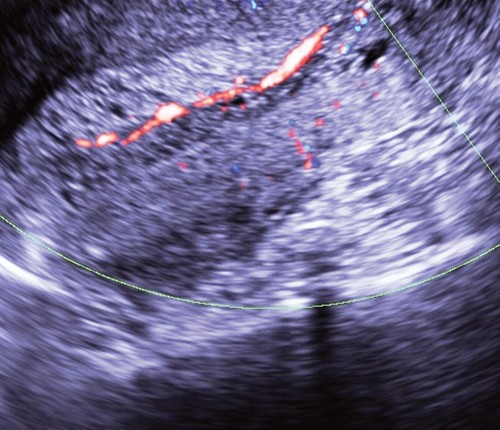

Отчасти это связано с тем, что для всех вариантов полипов шейки матки характерны небольшие размеры и одиночность поражения. К тому же, например, железистые полипы вообще не видны при ультразвуковом сканировании из-за того, что не только эхонегативная ткань железистых полипов сливается с изображением миометрия шейки матки и может быть неотличима от Ov. Nabotii (рис. 1), находящихся рядом с эндоцервиксом, но и из-за слизи в просвете шеечного канала.

Рис. 1. Парацервикальные кисты с содержимым различной эхоструктуры.